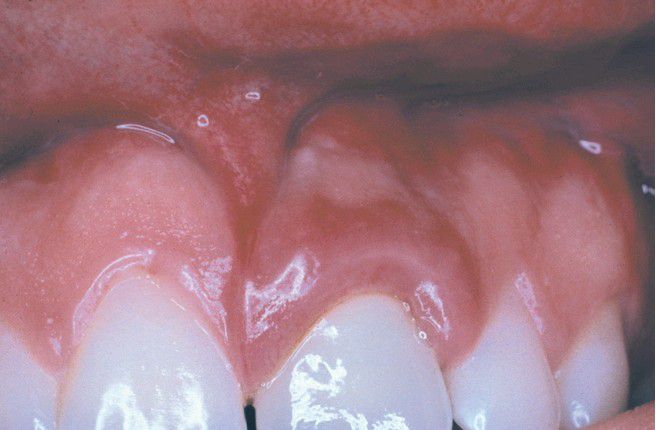

Granulomatous Gingivitis

. Localized enlarged and erythematous gingiva associated with the maxillary left central incisor. The alterations developed shortly after placement of a porcelain-fused-tometal (PFM) full crown and were not responsive to conservative local therapy.